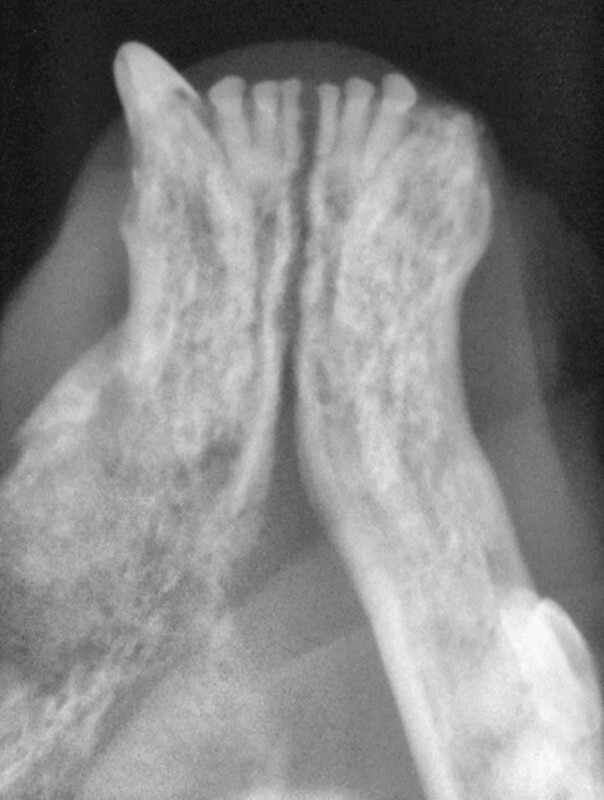

Dentale Röntgenaufnahmen sind gut geeignet zur Darstellung kleinerer Kieferabschnitte, ersetzen jedoch bei der diagnostischen Aufarbeitung von oralen Neoplasien nicht die Computertomografie. Die bei felinen Zahnpatienten routinemäßig angefertigten intraoralen Dentalröntgenaufnahmen aller Kieferabschnitte geben einen guten ersten Überblick über die Läsionen. Zahnröntgenaufnahmen sollten deshalb ohne Ausnahme angefertigt werden, auch von nicht zahntragenden Kieferabschnitten, um keine Befunde zu übersehen. Das Röntgenbild eines Patienten mit mandibulär lokalisiertem Plattenepithelkarzinom zeigt bereits die Destruktion des Knochengewebes mit Verlust der Kortikalis, während erst die Computertomografie das Ausmaß und die Ausdehnung der Läsion zeigt ( [Abb. 7] und [8] ).